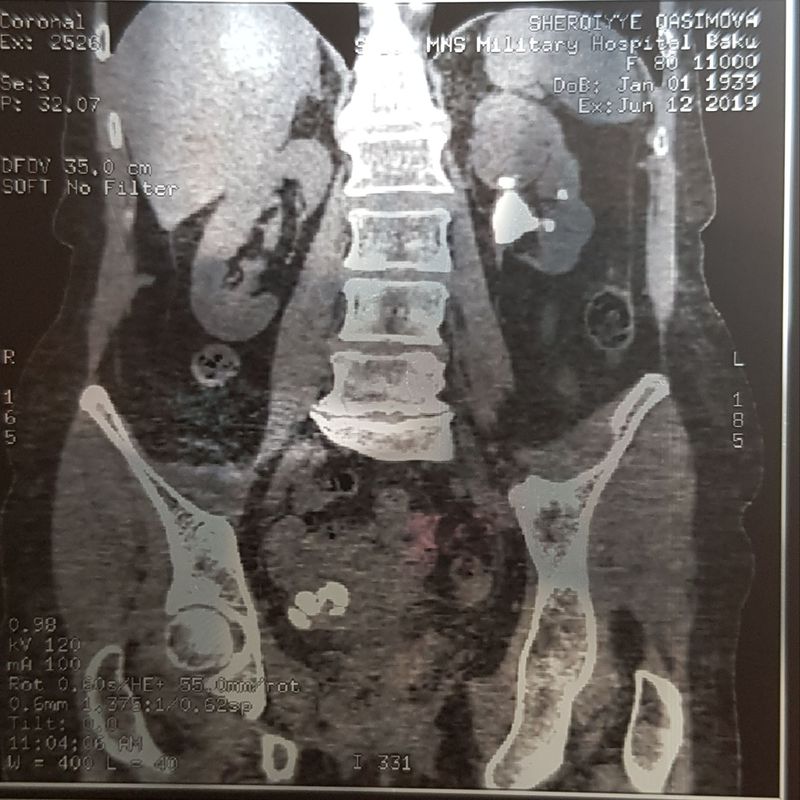

Kidney stone

Kidney

Urology

Stones

Also minimal scoliosis

Potential vertebral compression and Jack stones